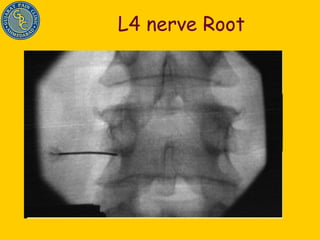

L4 nerve Root